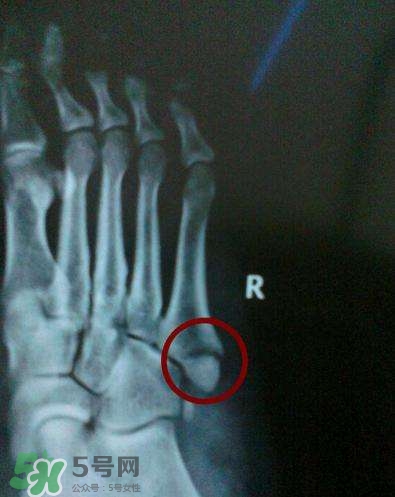

骨裂是骨折的一種,臨床上嚴格來說沒有骨裂這個說法, 骨裂只是普通的說法,是骨折的輕微狀態(tài),也就是骨頭裂開了,但是沒有移位,骨頭之間對位對線都是好的,所以一般不需要復位,只需要固定就可以,而骨折是一大類,包括沒有移位的骨折,也包括有移位的骨折。

一般骨裂分為移位骨裂和無移位骨裂、關節(jié)內骨裂和關節(jié)外骨裂,一般骨裂4-6周軟骨愈合,3月以上骨性愈合,不愈合的很少見,但是畸形愈合的較多見。但是這也不是絕對的,需要看骨裂的具體的部位損傷的程度。